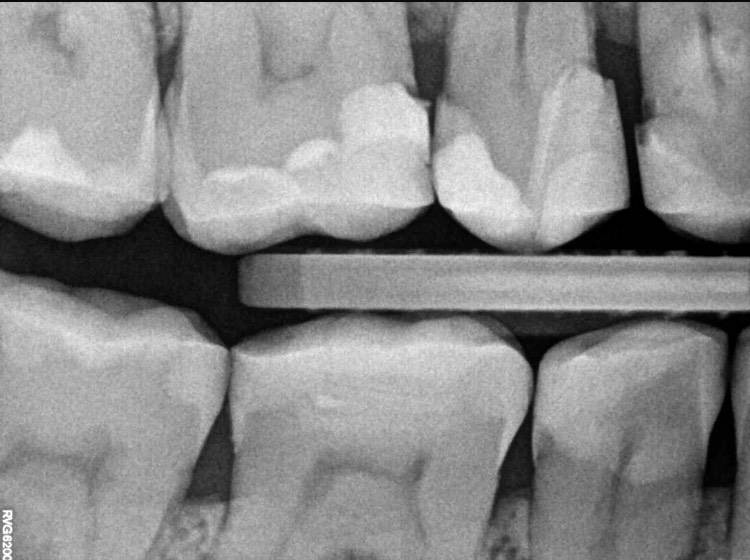

После удаления нервов у зума странная чувствительность когда касаешься наружной стенки водишь по ней ногтем … больновато сравнимо с оголенной шейкой зуба, на других поверхностях зуба норм. Снимки в хронологии прилагаю последний снимок спустя несколько месяцев94B0418C-0671-4347-824E-2BED80137804.jpeg.b4e6cccb387c9e1b58de0eb9e369f2d7.jpeg94B0418C-0671-4347-824E-2BED80137804.jpeg.b4e6cccb387c9e1b58de0eb9e369f2d7.jpeg924477BE-6116-4211-BAB9-431D846594C7.jpeg.8483250f5593afac6ce90d406c59f524.jpeg